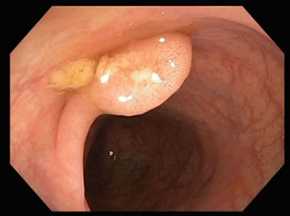

Premalignant lesions are described in terms of number, shape, size, location, histological type, and degree of malignancy. In terms of shape, the polyps were sessile, semipediculated or pedicled, round-oval, or polylobate (Figure 4).

B | |

C | D |

Fig. 4 Endoscopic appearance of polypsA – sessile polyp; B – semipediculated polyp; C – pedunculated polyp; D – voluminous villous polyp | |